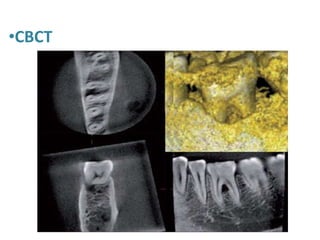

•CBCT

5- Radiographs • DigitalRadiography Dark and light bands are visualized on the X-ray film, where the dark bands represent aries